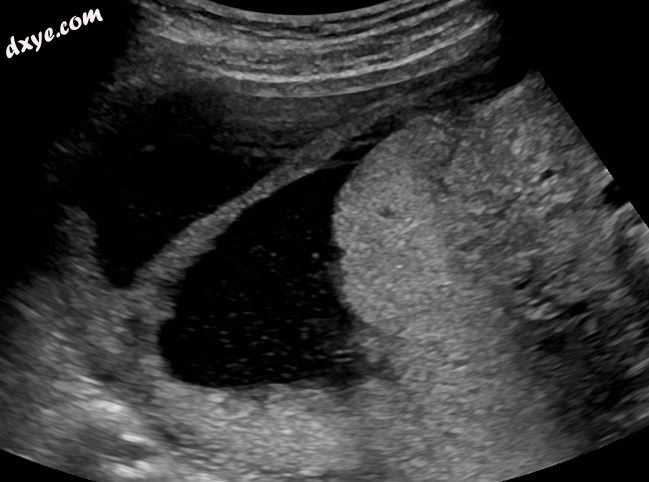

Ultrasound view..jpg

超声视图。

典型的是发生妊娠事件,然后进行D&C导致继发性闭经或月经少的病史。宫腔镜检查是诊断的金标准。[13]通过超声宫腔造影或子宫输卵管造影成像可以揭示瘢痕形成的程度。超声不是诊断阿舍曼氏综合症的可靠方法。激素研究显示正常水平与生殖功能一致。